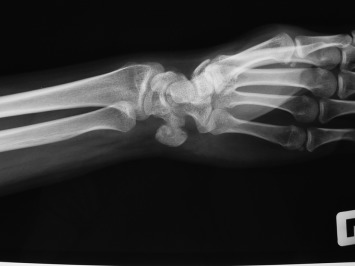

Pain was localized over ulnar styloid and pisiform bone by palpation. Initial X-rays did not detect any abnormality. After 1 month of rest, cold compression and NSAIDs, his complaints were the same and became resistant to NSAIDs. Magnetic Resonance Imaging (MRI) was ordered and signal intensity increase in triangular fibrocartilage complex (TFCC) along with medullary edema of the pisiform was reported. Although conservative treatment was started, the patient did not come back for 8 months. Then, he was admitted again to our institution because of unrelieved pain and progressively decreased ability to use his wrist in daily activities. Anteroposterior, lateral and 30° of supination X-rays (Fig. 1 ) and Computed Tomography (CT) with 3-D reconstruction (Fig. 2 ) revealed a sclerotic lesion surrounded by lucent area in dorsal and radial part of the pisiform suggestive of OO. MRI of the wrist revealed regression of medullary edema of the pisiform and normal appearing TFCC. Open excision and curettage of the lesion was decided.

Fig. 1

Fig. 1.

30° of supination view of the pisiform before the operation.